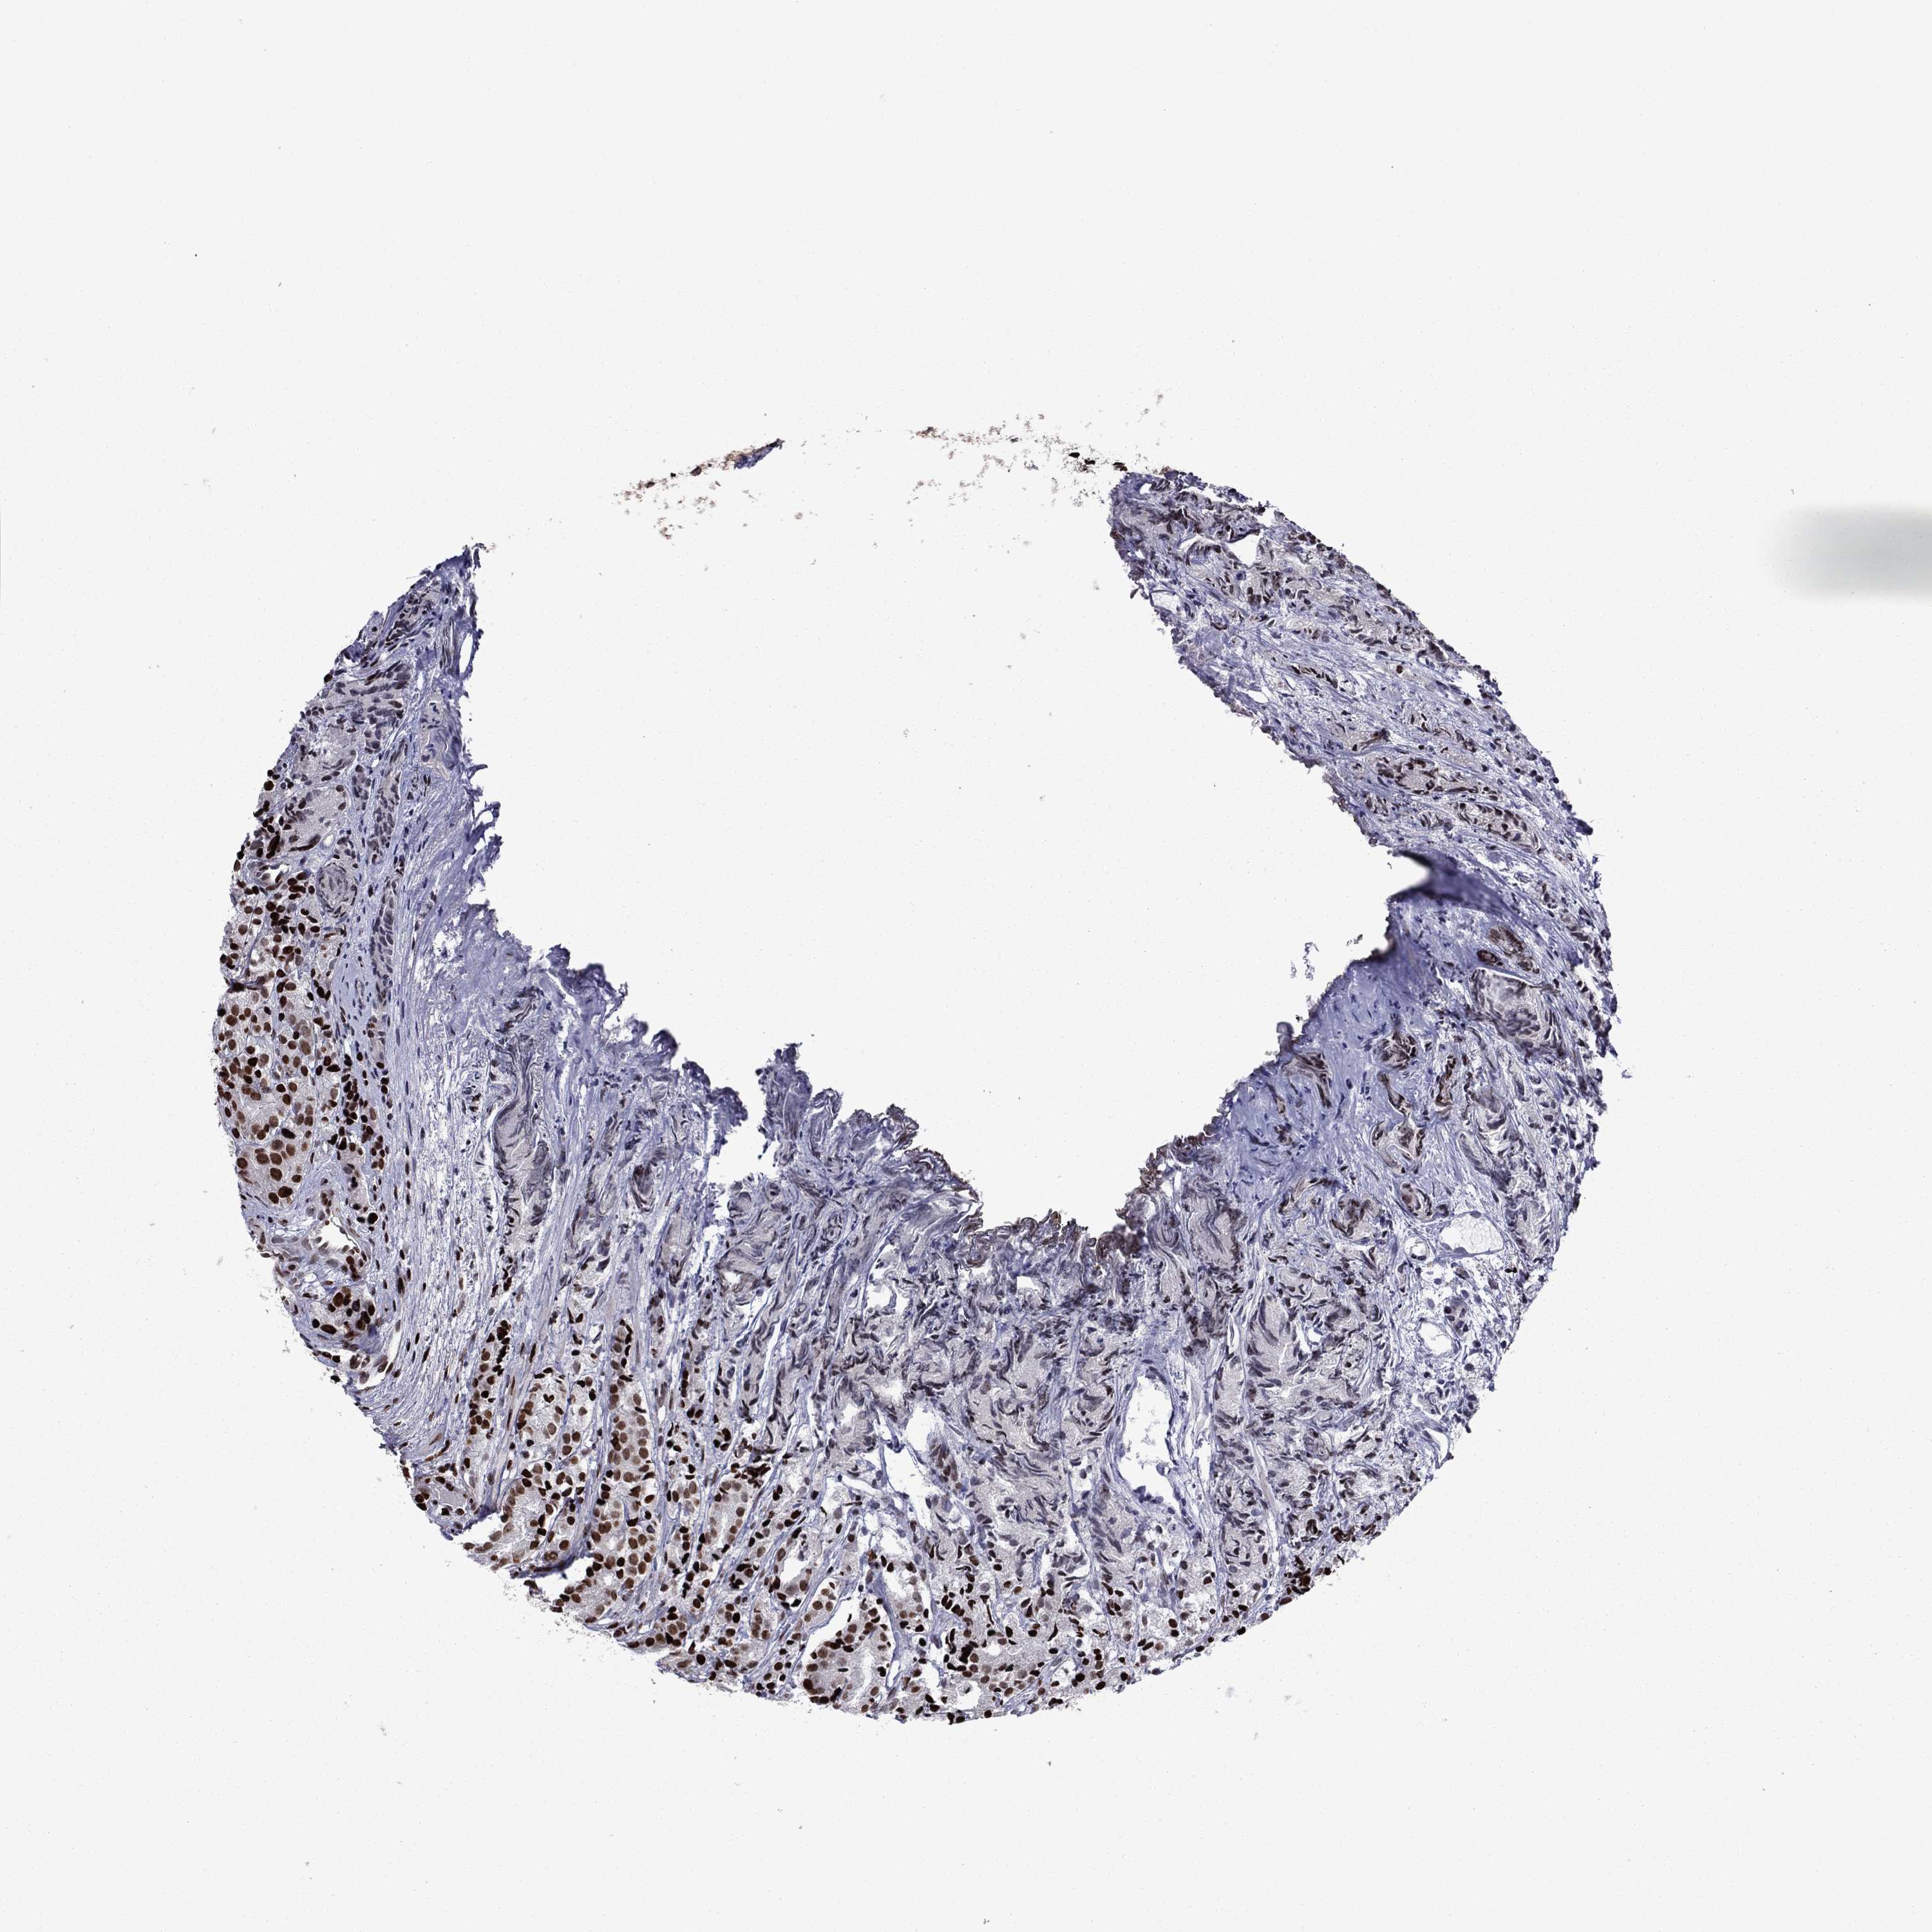

PROSTATE CANCER - Protein expressioni

A mouse-over function shows sample information and annotation data. Click on an image to view it in a full screen mode. Samples can be filtered based on level of antibody staining by selecting one or several of the following categories: high, medium, low and not detected. The assay and annotation is described here.

Antibody stainingi

Antibody staining in the annotated cell types in the current human tissue is reported as not detected, low, medium, or high, based on conventional immunohistochemistry profiling in selected tissues. This score is based on the combination of the staining intensity and fraction of stained cells.

Each image is clickable and will lead to virtual microscopy that enables deeper exploration of all samples and also displays staining intensity scores, fraction scores and subcellular localization as well as patient and tissue information for each sample.

Antibody HPA028516

Antibody HPA073571

Staining

High

Medium

Low

Not detected

Intensity

Strong

Moderate

Weak

Negative

Quantity

>75%

75%-25%

<25%

None

Location

Nuclear

Cytoplasmic/membranous

Cytoplasmic/membranous,nuclear

Adenocarcinoma, High grade

Adenocarcinoma, Low grade

Adenocarcinoma, Medium grade

Adenocarcinoma, NOS